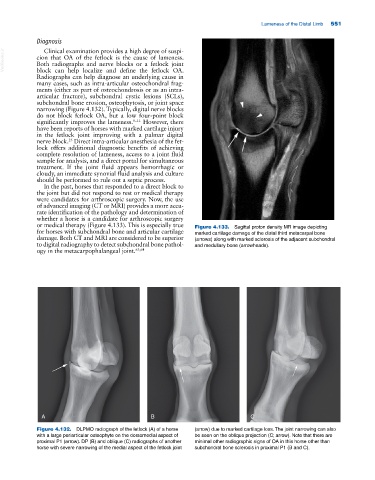

or medical therapy (Figure 4.133). This is especially true Figure 4.133. Sagittal proton density MR image depicting

for horses with subchondral bone and articular cartilage marked cartilage damage of the distal third metacarpal bone

damage. Both CT and MRI are considered to be superior (arrows) along with marked sclerosis of the adjacent subchondral

to digital radiography to detect subchondral bone pathol- and medullary bone (arrowheads).

ogy in the metacarpophalangeal joint. 63,64